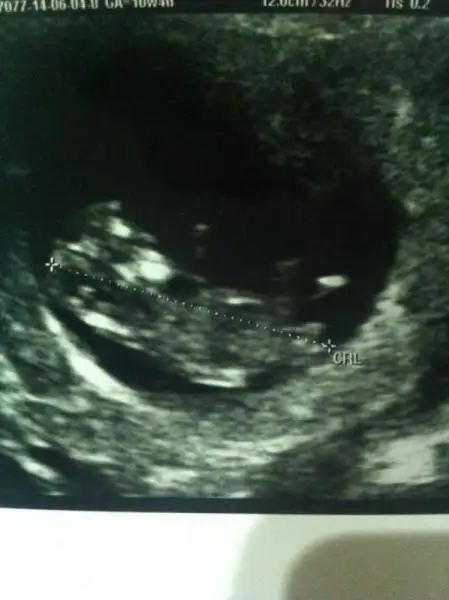

dr soylemeden siz gorun genital nub teorisi ( bebegin cinsiyeti)

Bnm 100 msjim olmadigi icin fotograf yukleyemiyorum..Anlayanlardan ALLAH rizasi icin rica ediyorum. faceden yuklesem bana yardimci olurmusunuz..cok merak ediyorum ..

kızlar rica ediorummm bi bakım bebegım burda 11+4 ...yorumlarınızı 4 gözle bekliorummmmm